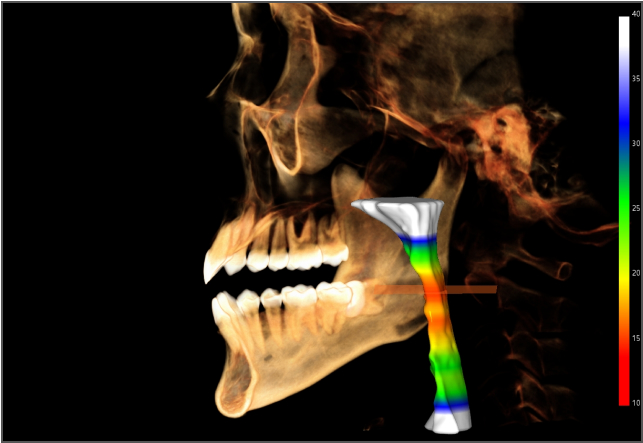

AI 加持,事半功倍 兰台医令的阅片软件包含 AI 神经管绘制、AI 气道分析、AI TMJ分析、AI 牙弓曲线、AI 正畸头影测量等智能图像处理功能,可大大提高诊断效率,实现更好的医患沟通,让医生事半功倍。